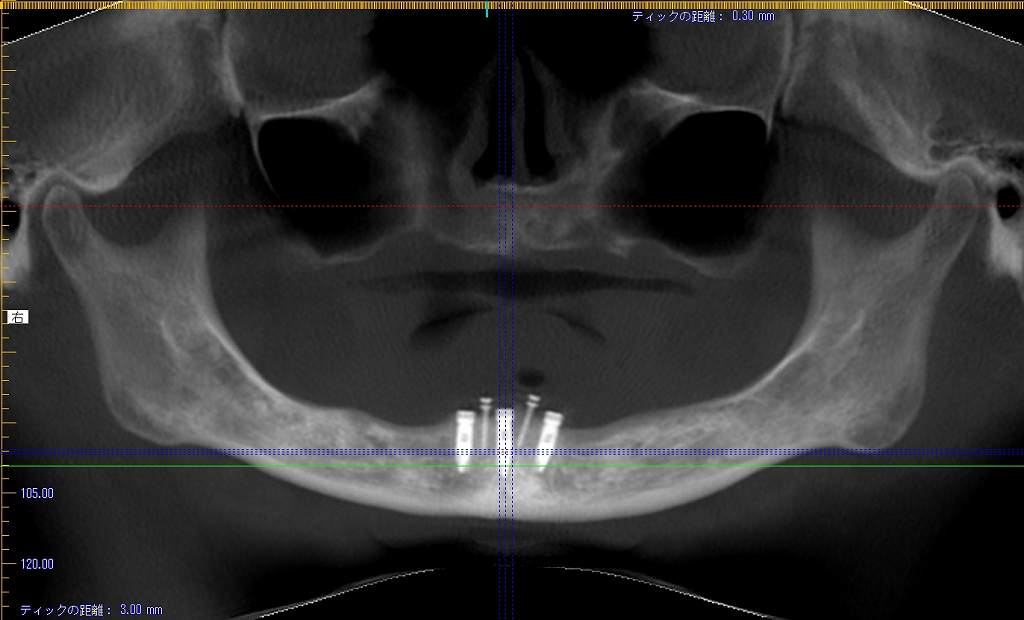

3本のインプラントになります

骨内に綺麗に埋まっています

右下の1番部、最前方部のインプラントになります